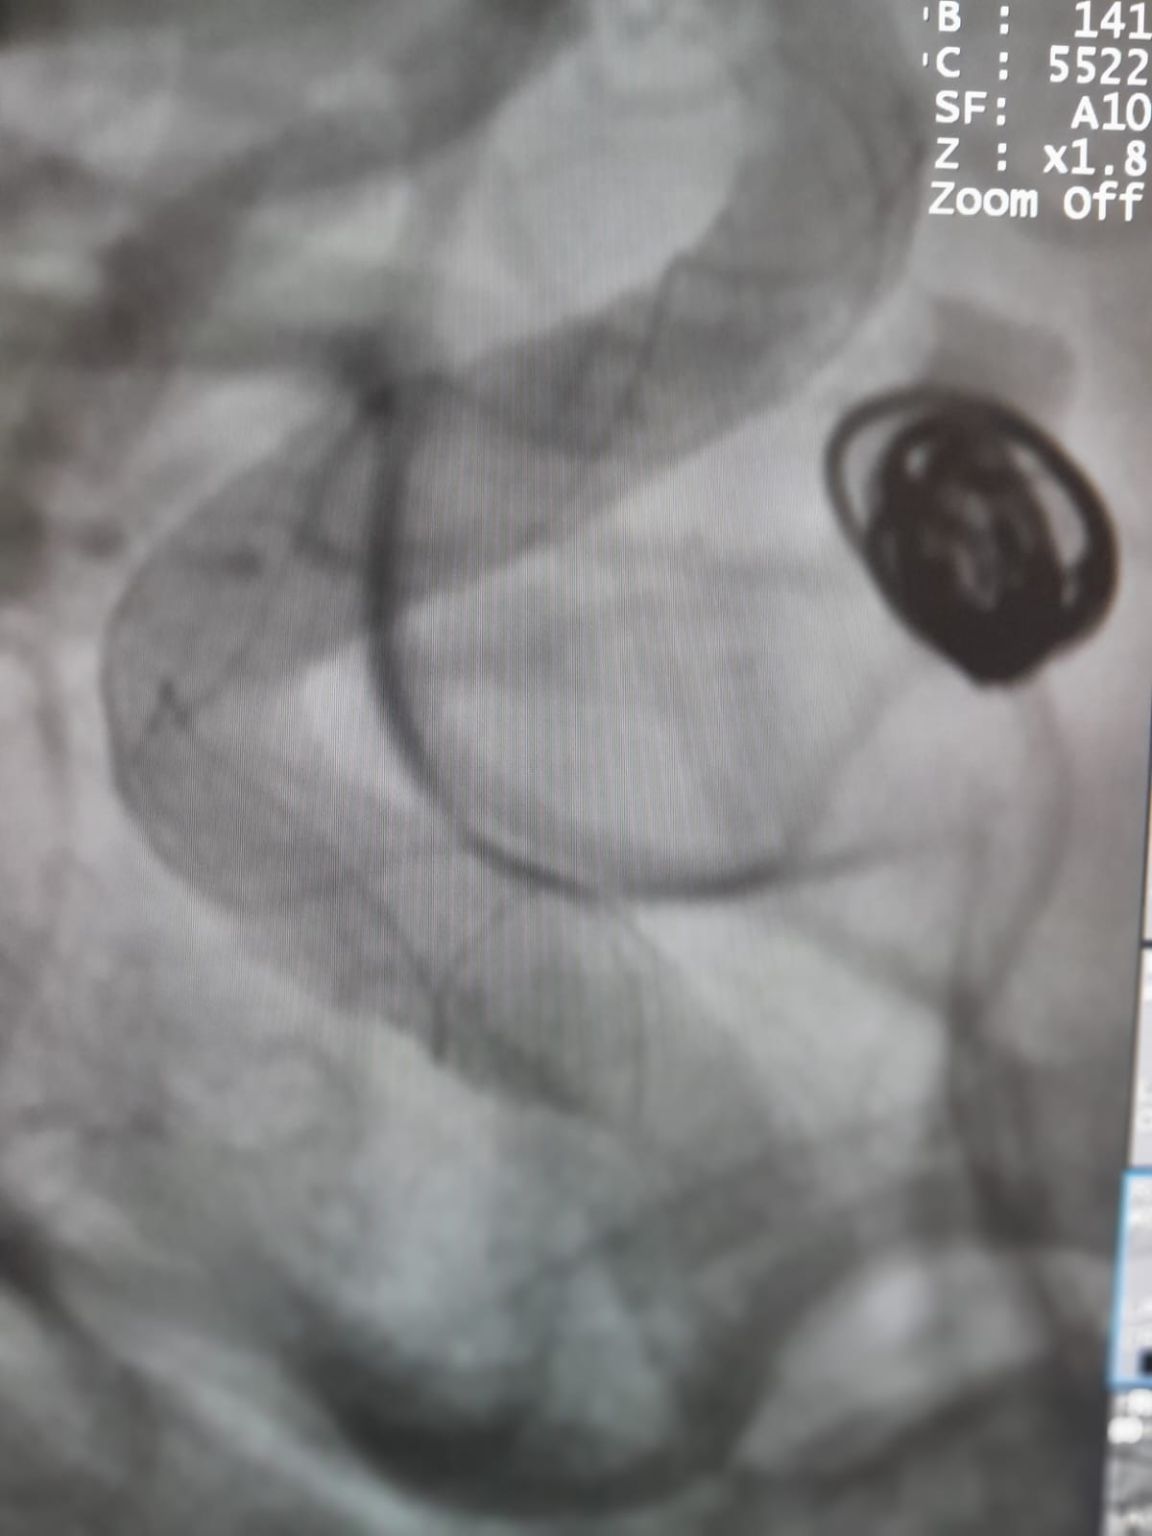

The vascular access was established and the team then successfully navigated the Frepass® Disposable Microcatheter (TJMC14) to the target site. Embolization was performed using three Perdenser® Embolic Coil System (TJCST4.508-3D, TJCST0306-3D, TJCST0206-3D) deployed with the Deromper® Coil Detachment Controller (TJCDC).